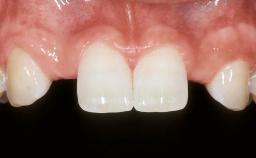

Esthetic Risk Assessment

| Esthetic Risk Factors | Low | Medium | High |

|---|---|---|---|

| Medical Status | Healthy | Compromised | |

| Smoking Habit | Non-smoker | Light smoker (< 10 cigarettes per day) | Heavy smoker (>= 10 cigarettes per day) |

| Patient's Esthetic Expectations | Low | Medium | High |

| Lip Line | No exposure of papillae | Exposure of papillae | Full exposure of mucosa margin |

| Periodontal Phenotype | Low-scalloped, thick | Medium-scalloped, medium-thick | High-scalloped, thin |

| Shape of Tooth Crowns | Rectangular | Triangular | |

| Infection at Implant Site | None | Chronic | Acute |

| Bone Level at Adjacent Teeth | <= 5 mm to contact point | 5.5 to 6.5 mm to contact point | > 7 mm to contact point |

| Prosthodontic Status of Neighboring Teeth | Virgin | Restored | |

| Width of Edentulous Span | 1 tooth (>= 7 mm) | 1 tooth (< 7 mm) | 2 teeth or more |

| Soft Tissue Anatomy | Intact | Defective | |

| Bone Volume | Horizontally and vertically sufficient | Horizontally deficient | Deficient vertically or deficient vertically AND horizontally |